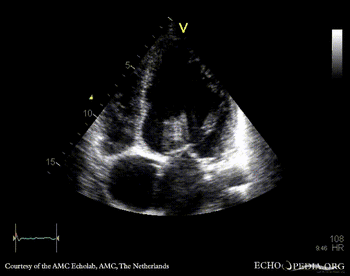

PLAX: dilated left ventricle, poor function, vegetation on aortic valve PLAX with zoom: vegetation on aortic valve